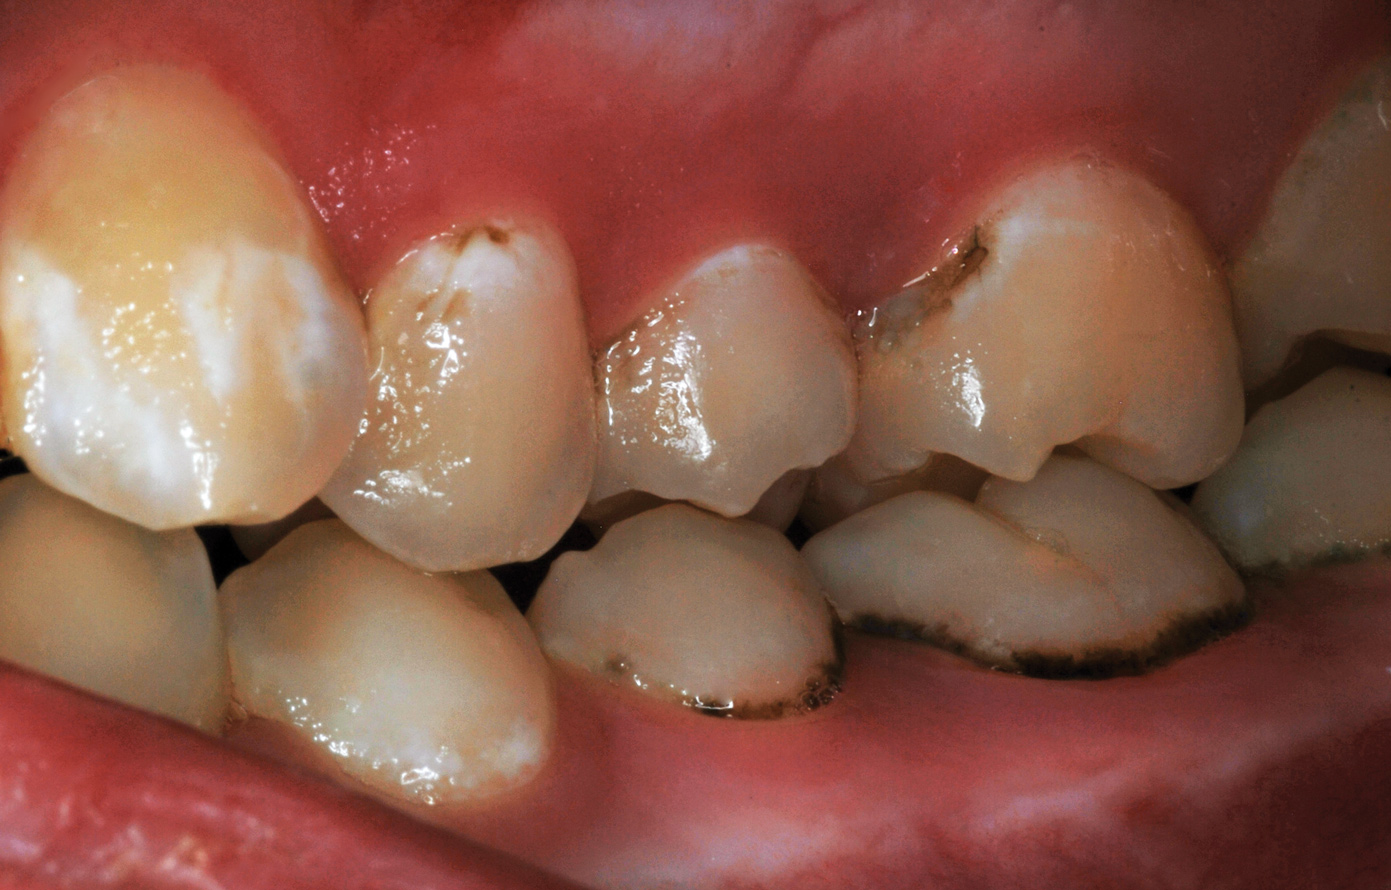

Fig 8. Caries prevention with SDF is critical on distal surfaces of primary second molars to avoid caries infection on mesial surfaces of permanent first molars. Note the Class 2 restorations in both primary molars in this 9-year-old patient whose first molar needed occlusal resin-based composite restoration.

Figure 8

Fig 19. Freshly exfoliated primary second molar with a mesial surface Class 2 caries lesion.

Figure 19